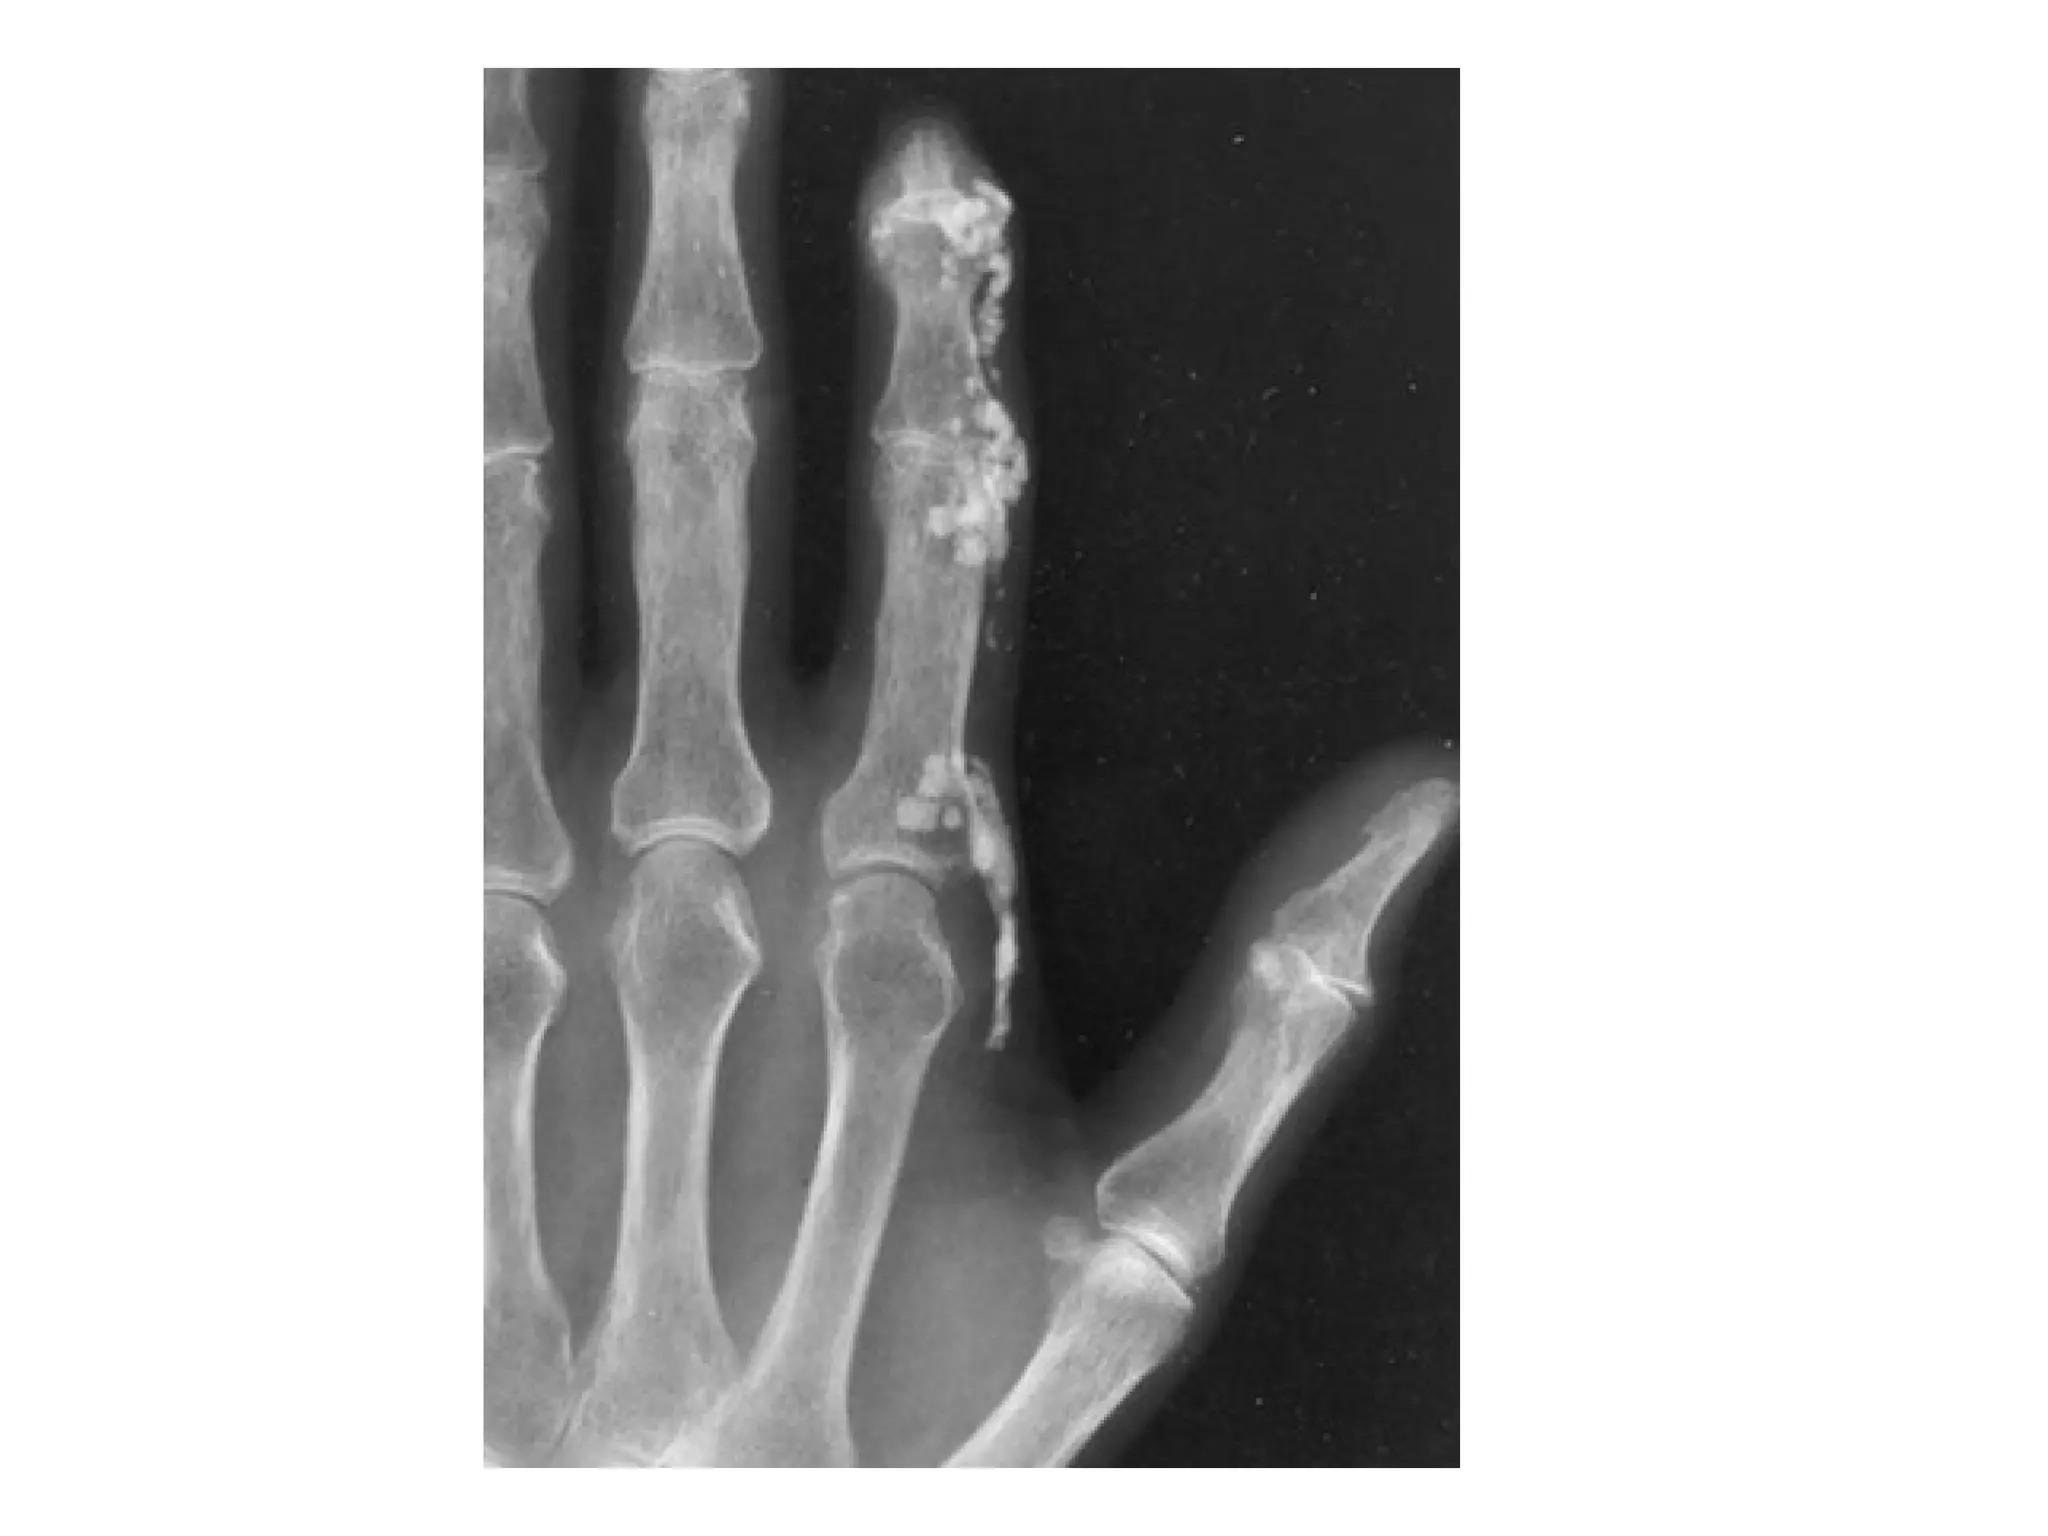

Large tophaceous deposits (white arrows) surrounding several of the

joints of the right hand , there are juxta-articular , punched-out lytic

erosions (white and yellow circles) and a lack of osteoporosis

characteristic of gout , the erosions are shown in close-up view

(blue arrows)